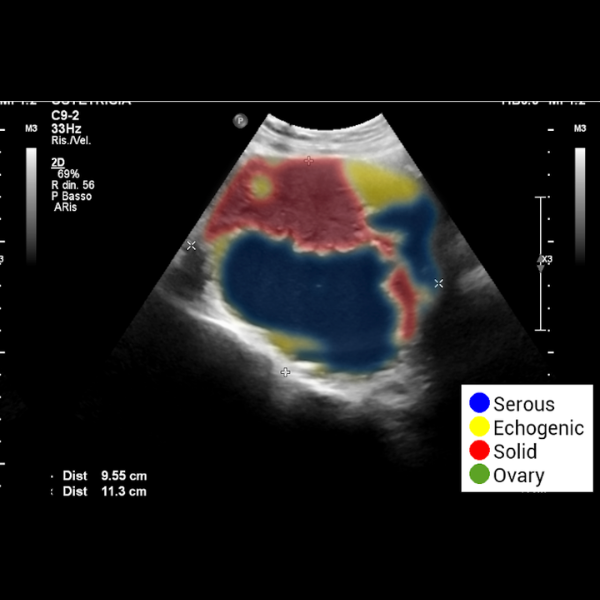

OvAi Focus utilizza algoritmi di AI addestrati per supportare la descrizione oggettiva delle strutture anatomiche, integrandosi nel flusso di lavoro senza interruzioni. Il software analizza l’imaging, identificando ed evidenziando l’organo e le strutture funzionali attraverso la definizione dei profili anatomici.

- Individua le aree solide e liquide della massa tramite codifica in falsi colori.

- Discrimina tra componenti anecogene, sierose e zone iperecogene

- Calcola il rapporto tra area solida e area totale (criteri IOTA) per una refertazione oggettiva.